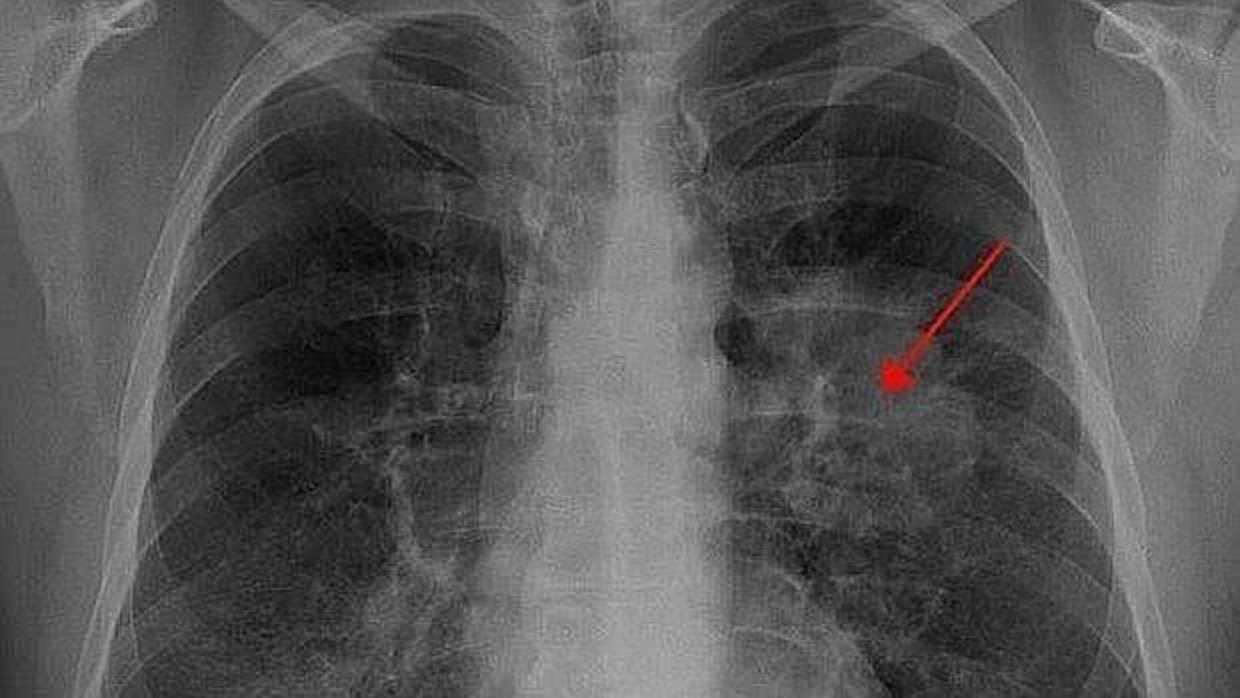

Radiografia de paciente con cáncer de pulmón ARCHIVO